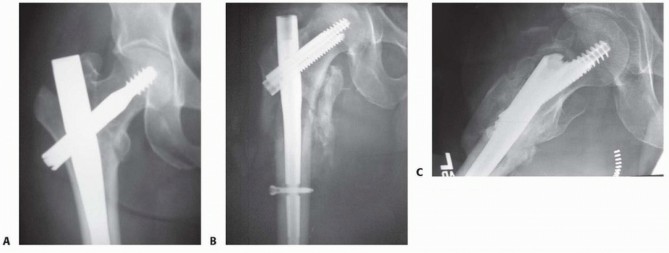

TECH FIG 4 • A. Insertion of reducer through channel reamer, lateral radiographic view. B. Reducer directed guide rod centered on lateral radiograph, avoiding anterior distal cortex. C. Diaphyseal reaming through channel reamer. D. Nail insertion. For trochanteric nail, the surgeon matches the curve of the nail with the proximal femur during initial insertion to minimize hoop stress at entry portal. The nail is rotated into correct position after 30% to 50% insertion. 4. ## Single-Screw or Single-Device Designs (Gamma, Stryker; IMHS, Smith & Nephew; TFN, DePuy Synthes) The center-center wire is inserted to within 5 mm of subchondral bone. Fracture reduction is confirmed and the length to lateral cortex is measured.

--- TECH FIG 5 • A. Gamma nail AP view with lateral trochanteric portal and center-center head screw position. B. Russell-Taylor IIB fracture with short InterTAN nail A C. Lateral view. If compression is desired (usually 5 mm), the surgeon reams for the screw and selects a screw 5 mm shorter than measured. For the TFN, the head is not reamed. The surgeon inserts the head fixation screw or nail to the desired depth; position is confirmed on AP and lateral C-arm views ( TECH FIG 5A). The option of compression and locking of the lag screw with a set screw within the nail is available on selected systems ( TECH FIG 5B,C).

### FIG 7 • Nail failures. A. Proximal screw cutout. B. Distraction nonunion with spiral blade nail construct. Functional recovery is poor in many patients, however, with more than 60% of patients failing to recover their preinjury level of function. 12 Mortality within the first year in patients older than 55 years is 20% to 30%. Many patients sustain progressive collapse of the hip into varus and shortening of the leg with the current generation of sliding hip screw fixation. 13 ## COMPLICATIONS

Loss of construct stability is one of the most common complications.

It is manifested by collapse of the screw and varus migration of the femoral head construct, with final cutout failure in the worst cases. This occurs to a small degree in all cases, as the sliding impaction was designed to minimize catastrophic cutout.

A center-center position of single-screw devices minimizes cutout. 4

Nail cutout is a much more serious complication, involving loss of fixation of the nail component in the proximal femur or periprosthetic femoral fracture with short nails; this will result in reoperation with locking construct plates or 95-degree blade plates, exchange for longer nails, or even prosthetic replacement in severe cases ( FIG 7A). If a lateral trochanteric portal was used, prepare for trochanteric accessory fixation

if arthroplasty is required. 6

Nonunion, although rare (1% in older patients), is usually treated with total hip replacement and grafting and implant revision in young patients ( FIG 7B).